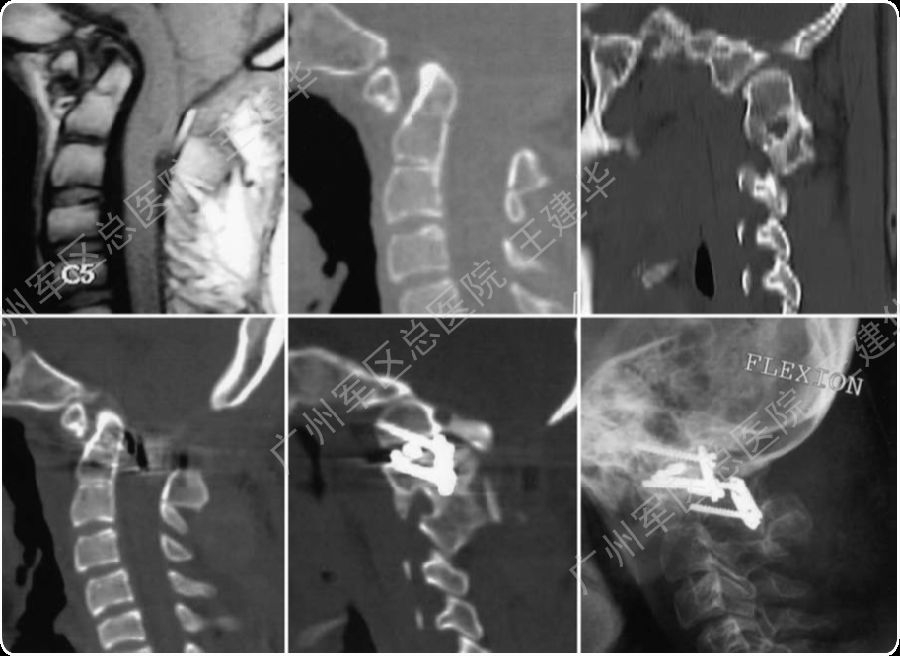

病例3

三维CT显示患者合并寰枕融合及C2/3融合,颅底凹陷

本例患者手术过程

手术前后对比

手术后2年复查的CT,显示侧块关节已经完全融合

病例4

颈椎MR检查提示:颈椎上端结构陷入枕骨大孔,脑干受压变形

手术复位过程

手术完成

可以看到:

陷入枕骨大孔的寰椎和齿突已经下拉复位,枕颈排列恢复正常

脑干压迫解除,延髓脊髓角恢复正常

手术后6年复查:

颅颈椎序列恢复正常并骨性融合